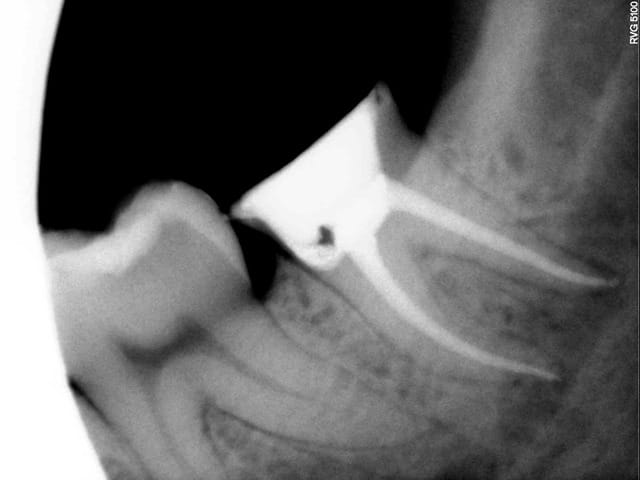

Pour confirmer ma réputation de coupeur de dent en quatre:

-suite à l'endo+rcr de la semaine dernière sur 46, ce matin: prep, pro 46 47 et amputation de la racine mésiale de 47 en 45min. Sur la radio, il reste encore un peu (;-)) de temp bond.

Retour dans 3 mois pour la suite des opérations.